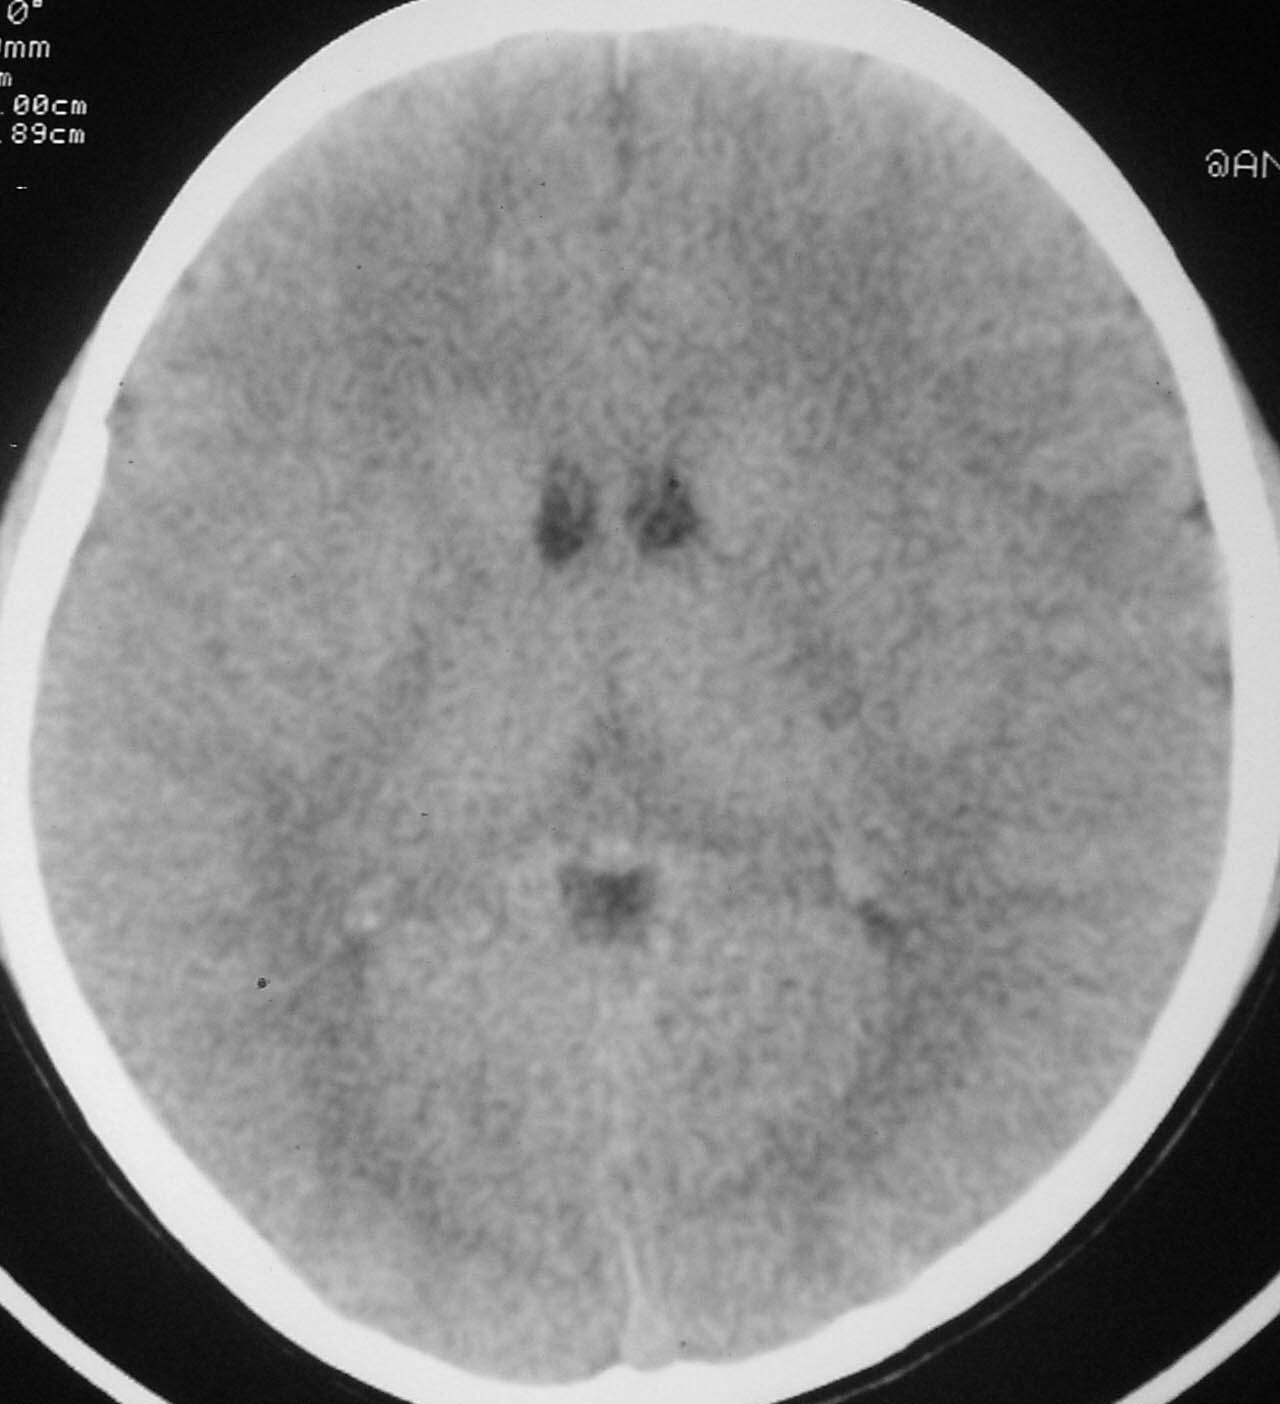

以下是引用余辉在2007-4-28 19:55:00的发言:[br]血管畸形?增强一下

以下是引用jw-830在2007-4-28 20:22:00的发言:[br]考虑血管畸形可能建议增强

以下是引用ysxyy在2007-4-29 21:14:00的发言:[br]像是假像,如果不放心可以偿试一下:[br]你用听眦线为基线扫一下,再用听眶线扫一下,就是说用不同的角度扫同一个地方;[br]看看有无变化,是不是有相同或相似的表现,即可鉴别;